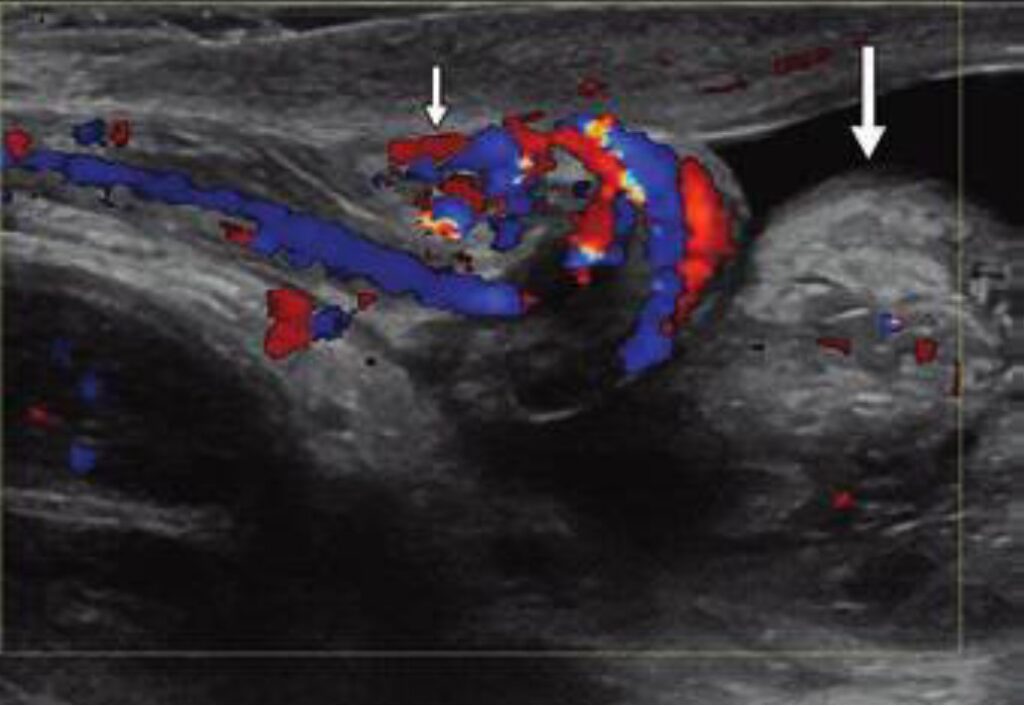

Pool Side: One of the most reliable indicators of torsion is the whirlpool sign, which represents the spiral twisting of the spermatic cord. Finding this sign above the testis (indicating at least a 360-degree twist) has been reported in the literature to have as much as 100% sensitivity and specificity for torsion.

Beware the Mimics: A common pitfall in scrotal imaging is misdiagnosing intermittent torsion as epididymitis. Following spontaneous detorsion, the ischemic tissue may respond with vasodilation, leading to hyperemia that mimics the appearance of infection. Additionally, twisting of the cord can create a heterogeneous “pseudomass” below the twist, composed of the congested epididymis and vascular bundle. Without careful evaluation of the cord’s proximal spiral twist, this can easily be mistaken for an inflamed epididymis.

Bottom Line: Even if flow seems normal today, repeat episodes of scrotal pain can’t be dismissed. A careful search for the whirlpool sign or an extratesticular pseudomass can be the key to saving a testis from future infarction.